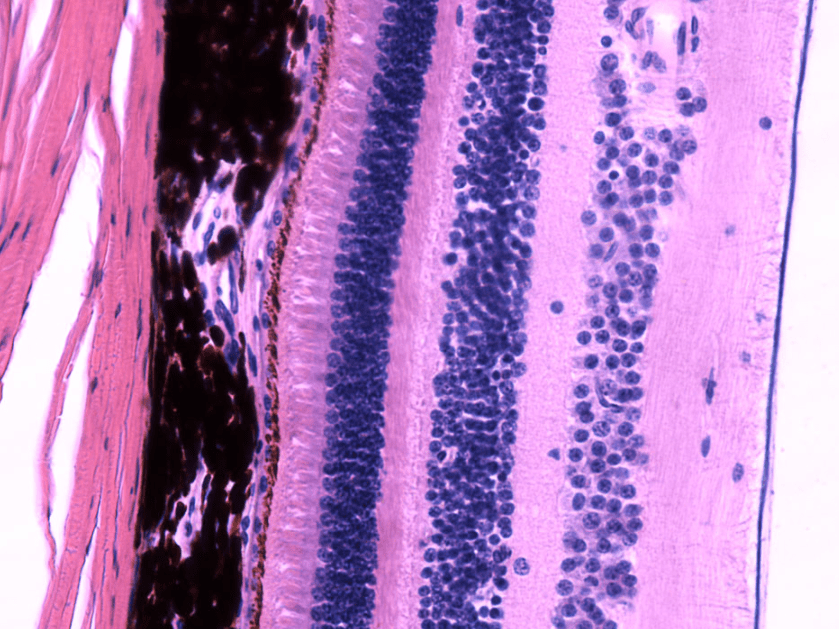

RETINA

- Epitelio pigmentario: Es la capa más externa de la retina.

- Capa de fotorreceptores: Está formada por los segmentos externos de los fotorreceptores.

- Limitante externa: No es una membrana, sino uniones tipo zónula adherens entre los fotorreceptores y las cél. de Müller.

- Nuclear o granular externa: Formada por los núcleos celulares de los fotorreceptores.

- Plexiforme externa: Sinapsis entre fotorreceptores y las cél. bipolares.

- Nuclear o granular interna: Encontramos núcleos celulares de las cél. bipolares, las cél. horizontales y las cél. amacrinas

- Plexiforme interna: Sinapsis entre células bipolares, amacrinas y ganglionares.

- Células ganglionares: Núcleos de las células ganglionares.

- Fibras nerviosas: Axones de cél. ganglionares.

- Limitante interna: Separa la retina del humor vítreo.